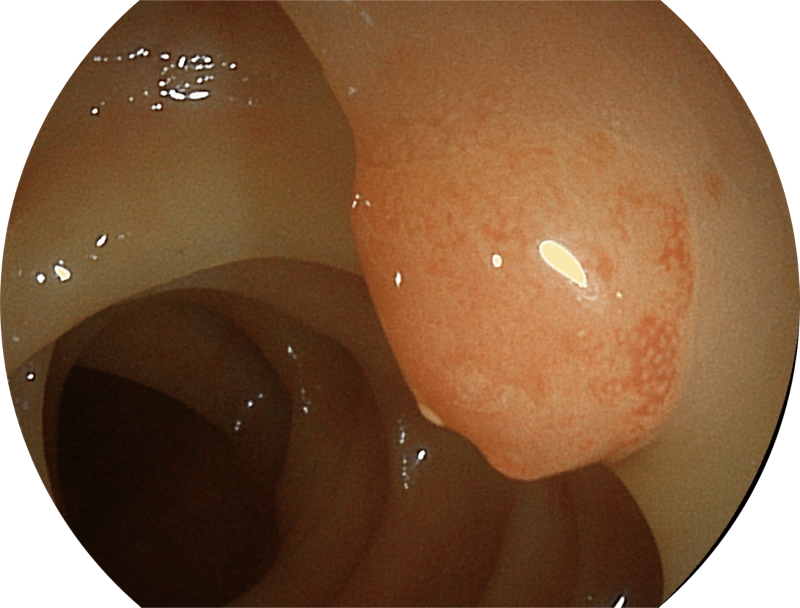

(Spectral Focused lmaging, SFI)

能够凸显黏膜浅层和中层血管轮廓,适用于中、远景观察下的病灶识别和早癌筛查。